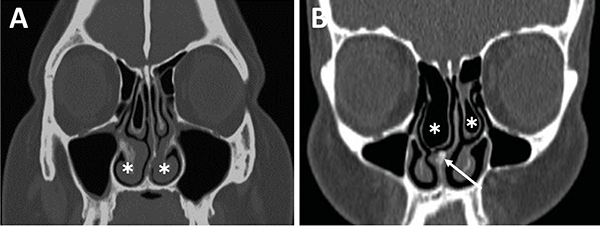

La evaluación del septum nasal podrá mostrar si presenta desviación o prominencias óseas que puedan dificultar el abordaje como también el tallado de un colgajo nasoseptal del lado elegido (fig. 9).[28] En caso de desvío septal se puede realizar septoplastia selectiva de la región desviada para logar un abordaje adecuado .

En referencia a las variantes turbinales se debe considerar la presencia de hipertrofia turbinal inferior y de cornetes medios bullosos (fig. 10). Ante la hipertrofia turbinal inferior será necesario realizar buena vasoconstricción preoperatoria asociada a luxofractura y lateralización para lograr un abordaje adecuado si es que no se asocia un tratamiento para la insuficiencia ventilatoria. Los cornetes medios bullosos representan una variante hipertrófica con neumatización de los mismos, los cuales podrán resecarse parcial o totalmente para lograr el correcto abordaje.

Figura 9: Desvío septal severo en TC cortes coronales. A) Inferior a fosa nasal derecha; B) Medio a fosa nasal izquierda.

Figura 10: Variantes turbinales en TC cortes coronales. A) Hipertrofia turbinal inferior (asteriscos blancos); B) Cornetes medios bullosos (asteriscos blancos) y desvío septal-espolón (flecha blanca).